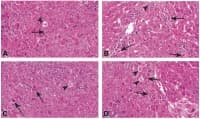

Мастнотъканна некроза

Мастнотъканната некроза е форма на некроза, която се характеризира с действието на храносмилателните...